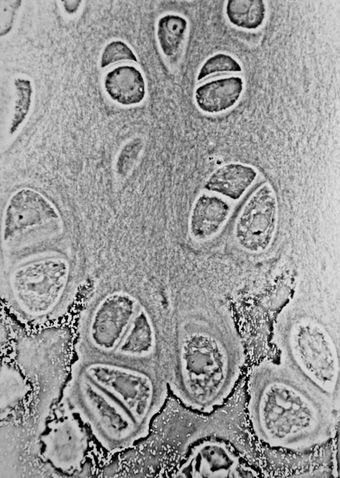

Light micrograph of hyaline cartilage showing its chondrocytes and organelles, lacunae and matrix.

الخلية الغضروفية إنگليزية: Chondrocyte وهي الخلية الوحيدة الموجودة في الغضروف السليم. تنتج وتحافظ علي المصفوفة الغضروفية التي تتكون أساسا من الكولاجين و البروتوجليكان. على الرغم من استخدام كلمة أرومة غضروفية يكون شائع كوصف للخلية الغضروفية غير الناضجة، وهذا المصطلح غير دقيق لأن خلايا السلف الغضروفية (الخلايا الجذعية الوسيطة) يمكن أن تتفرق إلى أنواع متعددة من الخلايا بما في ذلك خلايا بانيات العظم.

الخلايا الغضروفية تتمايز إلى ما يدعى بانيات الغضروف حيث تصنع غضروف خارج المصفوفة، تتكون الخلفية من مواد (بروتوجليكان، جليكوز امينو جليكان ذات الأسموزية المنخفضة) والألياف. بانيات الغضروف تصبح خلية غضروفية ناضجة عادة ماتكون غير نشطة، لكن ما تزال تفرز وتدرك المصفوفة معتمدة على الظروف.